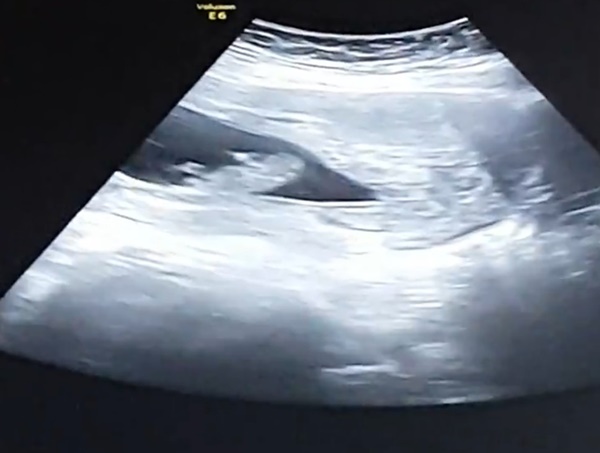

Merhaba, bebeğinizin cinsiyeti hakkında yorum yapamıyoruz çünkü yüklemiş olduğunuz görsel nub çıkıntısı hakkında bilgi vermiyor. Değerlendirme yapabilmek için görselin aşağıdaki gibi net ve anlaşılır olması gerek. Sağlıklı gebelik süreci diliyorum..

nub teorisi.jpg